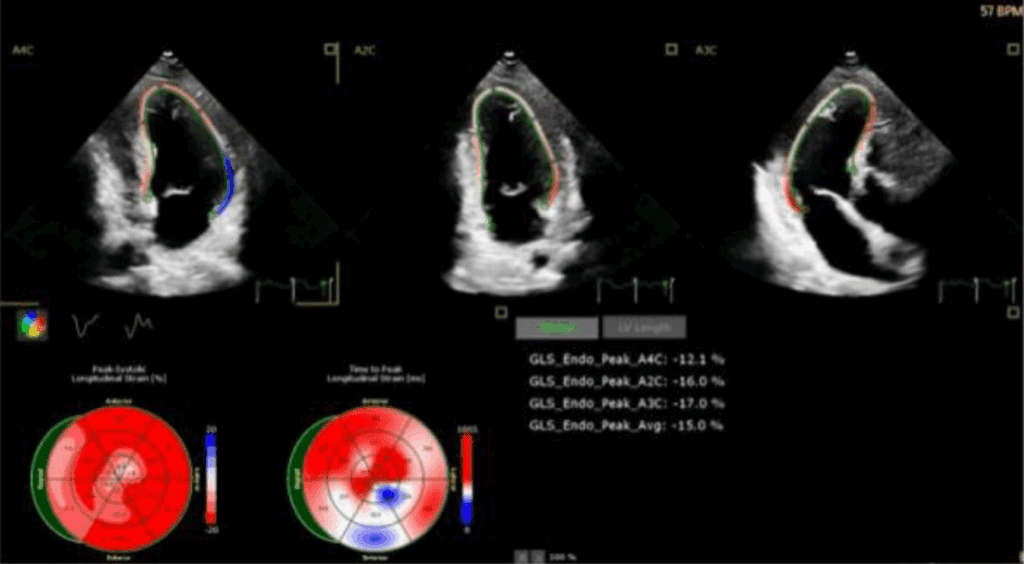

Odkształcenie mięśnia sercowego (strain) jest metodą diagnostyczną oraz coraz lepiej udokumentowanym parametrem prognostycznym, który uzupełnia standardowe przezklatkowe badanie echokardiograficzne (ang. transthoracic echocardiography – TTE).